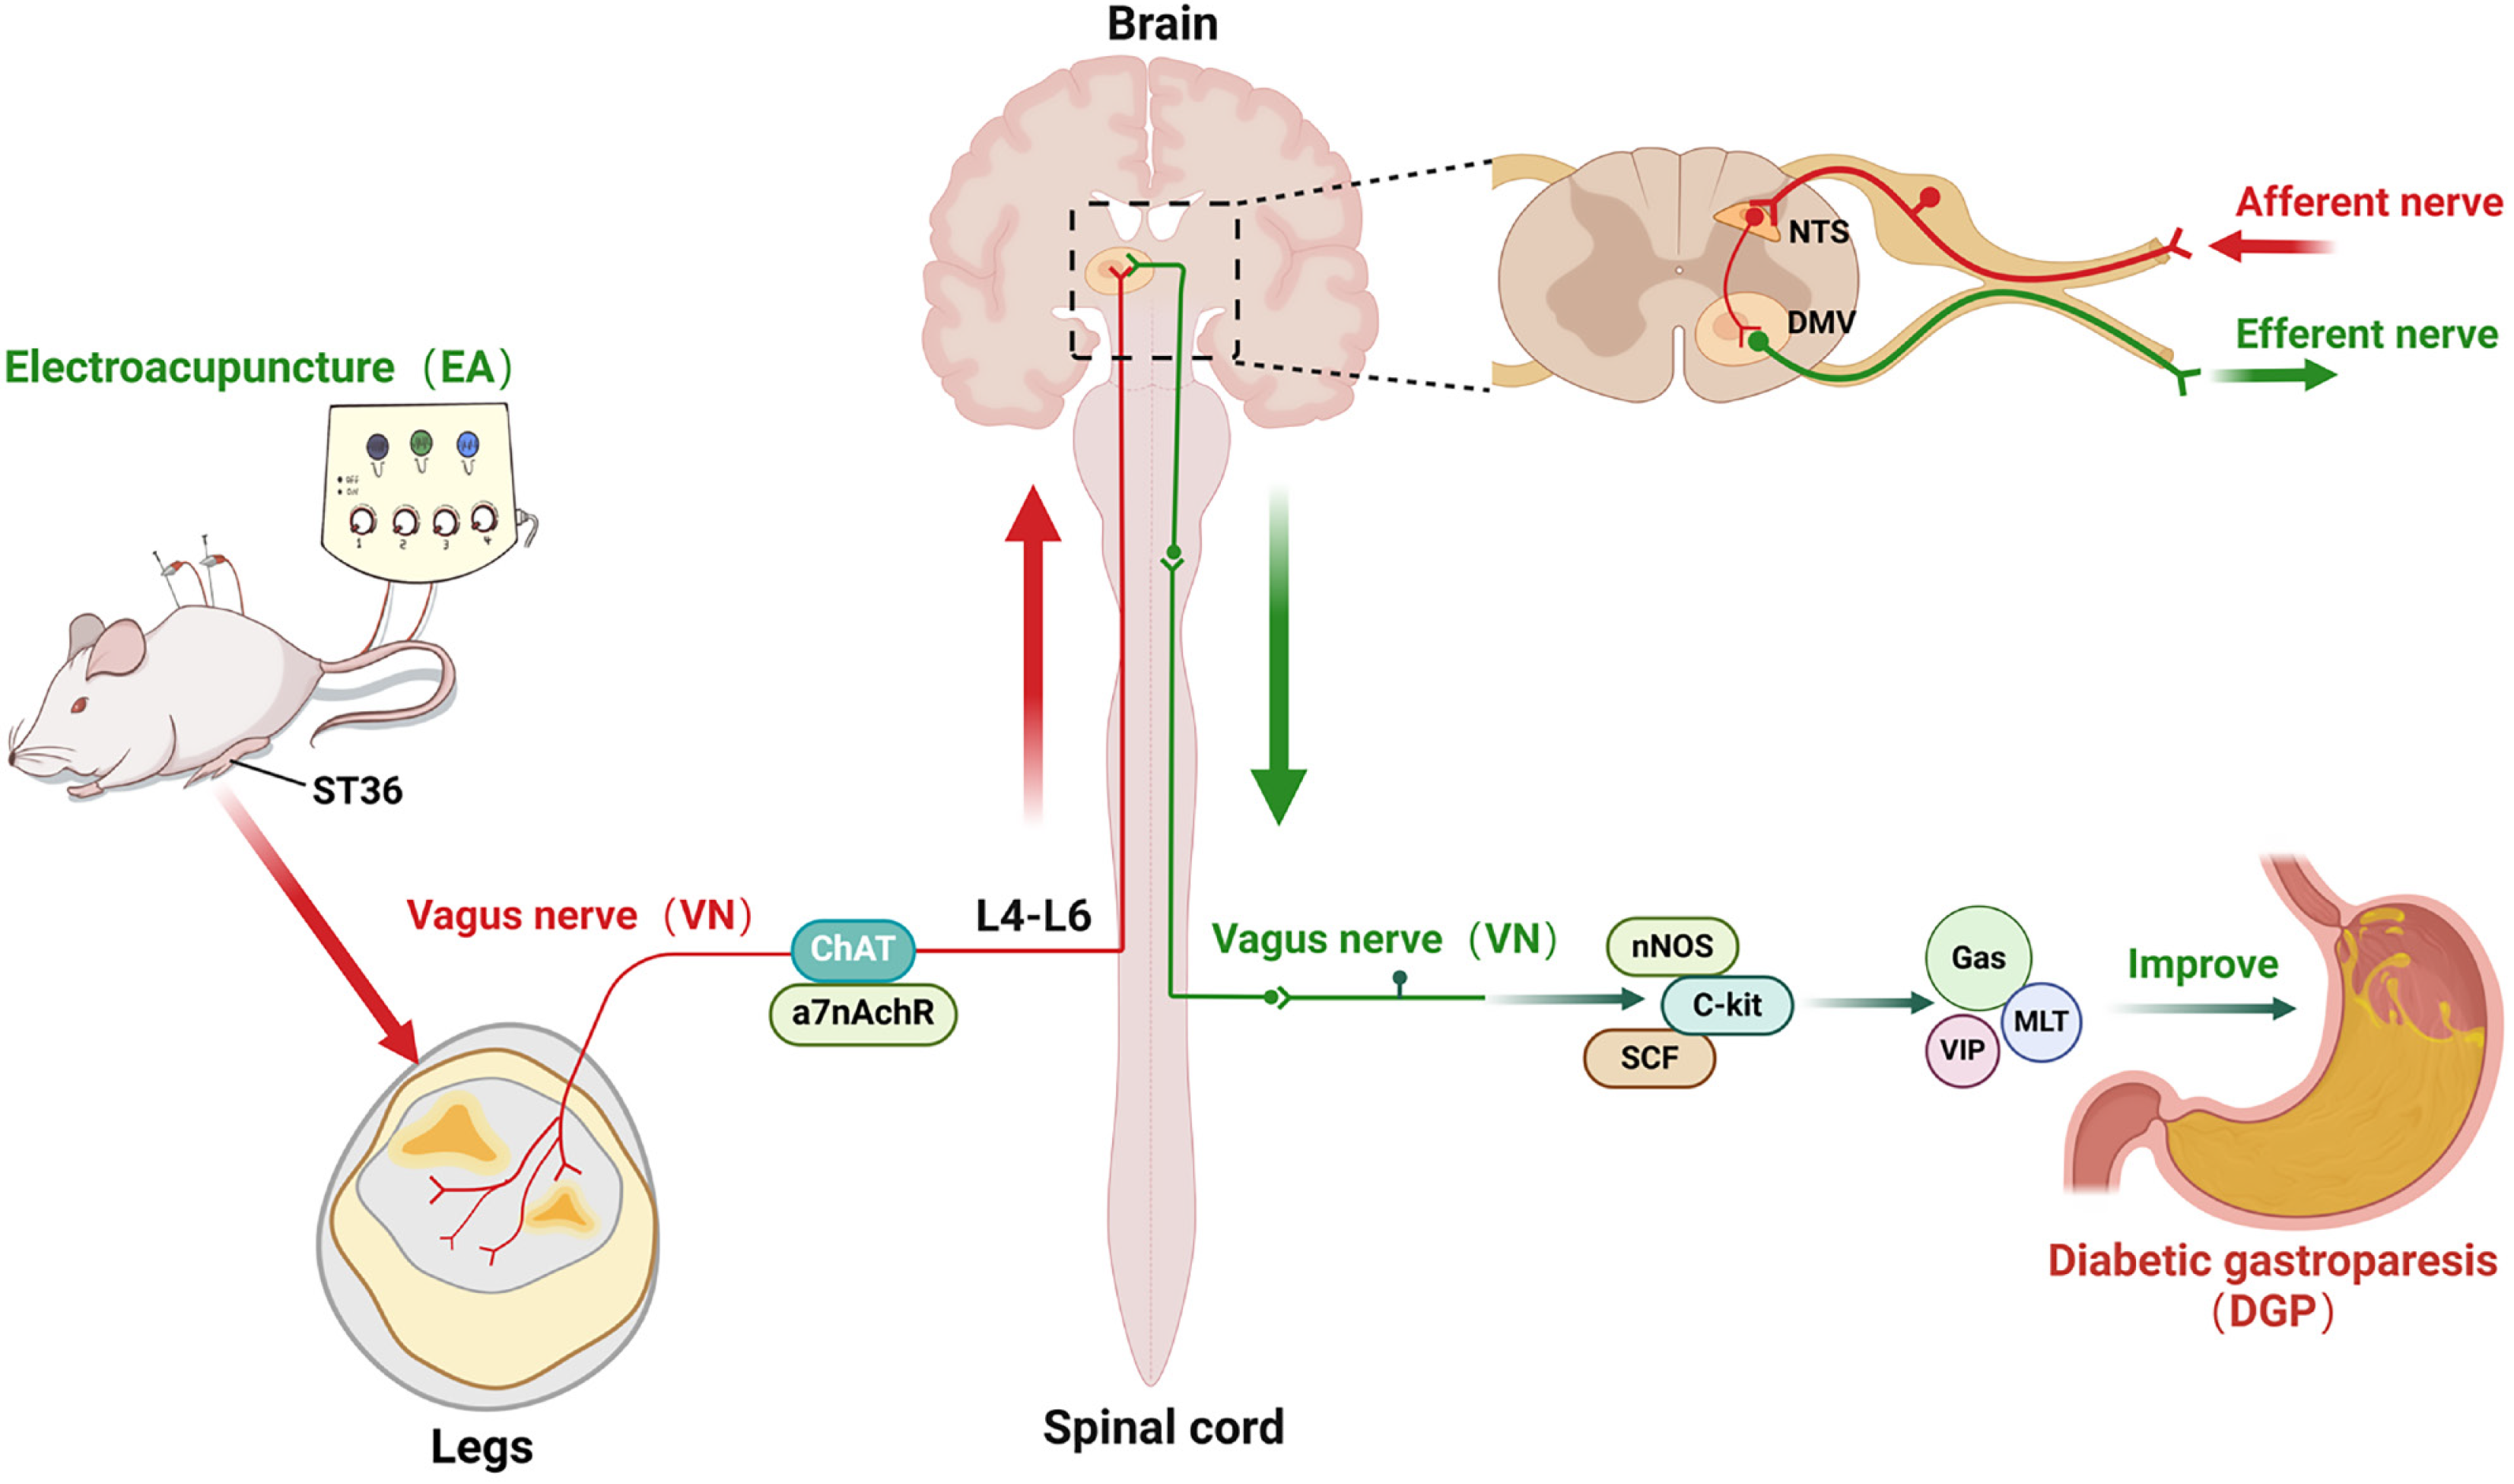

The study found that EA significantly increased the rate of gastric emptying, restored the slow-wave rhythms of the stomach, and improved the architecture of the smooth muscles in the stomach. This was evidenced by a reduction in inflammatory infiltration and an increase in the expression of nNOS, C-kit, and SCF. Mechanistically, EA activated vagal targets (ChAT and α7nAChR) at ST36, transmitting signals via spinal segments L4-L6 to the NTS, subsequently regulating gastrointestinal peptides (Gas, MLT, VIP) and restoring interstitial cells of Cajal (ICCs) function via subdiaphragmatic vagal efferent pathways. It is crucial to note that subdiaphragmatic vagotomy led to the abrogation of EA-induced enhancements in gastric motility and ICC recovery, thereby confirming the indispensable role of vagal efferent signalling.

EA provides a novel molecular mechanism for improving gastrointestinal motility in DGP via a peripheral stimulation (ST36), spinal afferent (L4-L6), brainstem integration (NTS), vagal efferent (gastric) circuit.

In order to elucidate the afferent neural pathways underlying EA-mediated gastric motility modulation in DGP rats, the ChAT inhibitor AP or the agonist PA was injected into the ST36 acupoint area and ChAT and α7nAChR protein expression was quantified across three key sites (Figures 4, 5 and 6): The ST36 acupoint skin, the spinal L4-L6 segments and the NTS (Figures 4A, 5A and 6A). Western blot analysis revealed significantly elevated ChAT levels in DGP rats compared to Sham controls across all sites (P < 0.05), with EA further amplifying ChAT expression (P < 0.05), mirroring trends observed in the PA group. However, the co-administration of AP with EA (EA + AP group) led to the abolition of this activation (P < 0.05; Figures 4B, 5B and 6B). In addition, EA induced an increase in α7nAChR expression in the ST36 skin, L4-L6 spinal region, and NTS (P < 0.05), an effect that was attenuated by AP co-treatment (P < 0.05; Figures 4C, 5C and 6C). Immunofluorescence analysis corroborated these observations. DGP rats exhibited reduced ChAT expression in ST36 skin, whereas EA and PA groups showed marked increases. AP administration nullified EA’s effects (Figure 4D). In the spinal L4-L6 segments, c-FOS immunostaining revealed robust neuronal activation in the EA and PA groups (P < 0.05), which was suppressed in the EA + AP rats (P < 0.05; Figure 5D). c-FOS +/ChAT + co-localization further confirmed that this activation was ChAT-dependent (Figure 5E). In the NTS, c-FOS expression was significantly elevated in the EA and PA groups (P < 0.05), with EA + AP rats showing reduced activation (P < 0.05; Figure 6D). c-FOS +/ChAT + co-expression mirrored these trends, demonstrating EA’s dual modulation of neuronal activity and cholinergic signalling (Figure 6E). The data taken together indicate that EA activates vagal ChAT/α7nAChR targets at ST36, transmitting signals via spinal L4-L6 afferents to NTS neurons, thereby restoring vagal tone in DGP.

Hierarchical vagal regulatory pathways involve brainstem nuclei, particularly the DMV and the NTS, which serve as central hubs for integrating gastrointestinal signals (e.g., stretch reflexes and satiety) and coordinating gastrointestinal motility. EA at ST36 has been shown to modulate neuronal activity in these regions through vagal afferent pathways[27,30]. For instance, retrograde tracing using cholera toxin or pseudorabies virus injected at ST36 revealed abundant labeled neurons in the NTS and DMV, confirming direct neural connectivity between ST36 and these nuclei[31]. Fang et al[32] demonstrated that EA at ST36 activates NTS neurons, subsequently enhancing vagal efferent activity to promote gastrointestinal peristalsis. Consistent with this, our findings showed EA-induced activation of c-FOS-labeled neurons in the NTS accompanied by synchronized ChAT upregulation, further supporting the cascade activation of vagal central circuits. It is crucial to note that the efficacy of these EA-induced effects is contingent on the integrity of the vagus nerve. SDV abolished EA’s therapeutic benefits on gastric emptying and gastrointestinal peptide secretion[33]. In a similar manner, Song et al[34] reported that vagal denervation negated EA’s efficacy in ameliorating post-burn gastric dysfunction. The present study revealed that vagotomy not only blocked EA’s prokinetic effects but also attenuated its regulation of smooth muscle-related factors and gastrointestinal peptides. Most notably, vagal ablation completely abolished EA-induced ChAT upregulation, underscoring the indispensable role of vagal efferent pathways in EA’s anti-DGP mechanisms.

In summary, EA has been shown to ameliorate DGP through a multi-level neural pathway involving peripheral acupoint (ST36), spinal cord (L4-L6), brainstem nuclei (NTS), target organ (stomach), with therapeutic efficacy strictly dependent on intact vagal circuitry. These findings provide novel insights into the neural mechanisms underlying EA’s improvement of gastric dysmotility in DGP, advancing research directions for non-pharmacological interventions. However, this study has limitations. While the investigation focused on elucidating the role of the NTS-vagal axis in EA-mediated improvements, alternative regulatory pathways, such as sympathetic innervation and inflammatory cascades-were not systematically explored, which may overlook potential cross-talk mechanisms between neural and immune systems in DGP pathogenesis. Future studies will prioritize dissecting these interactions to comprehensively map the neuromodulatory network underlying EA therapy.

This study elucidates the mechanism by which EA improves gastric dysmotility in DGP rats through multi-tiered validation of vagal pathways. Firstly, EA at the ST36 acupoint activates peripheral vagal targets, specifically ChAT, transmitting signals via spinal L4-L6 afferents to the central nervous system. Subsequently, at the brainstem level, these signals enhance vagal central drive by activating c-FOS-expressing neurons in the NTS. Finally, EA upregulates smooth muscle-related factors (nNOS, C-kit, SCF) and promotes gastrointestinal peptide secretion, ultimately restoring gastric emptying (Figure 9). In this study, we systematically revealed for the first time the mechanism by which EA improves gastrointestinal motility in DGP through an integrated regulatory circuit of peripheral stimulation, spinal afferents, brainstem integration, vagal efferent, which provides a novel molecular mechanism for the treatment of DGP by EA.